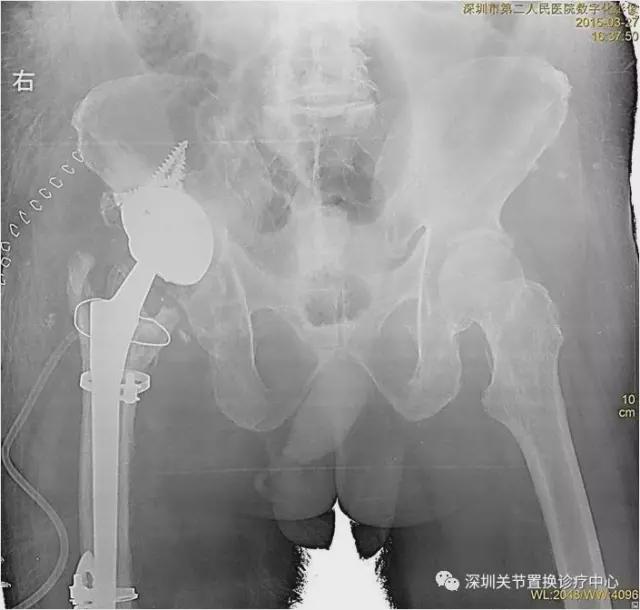

术前X线片

我的天,松动!感染!脱位!人工髋臼都翻转啦!